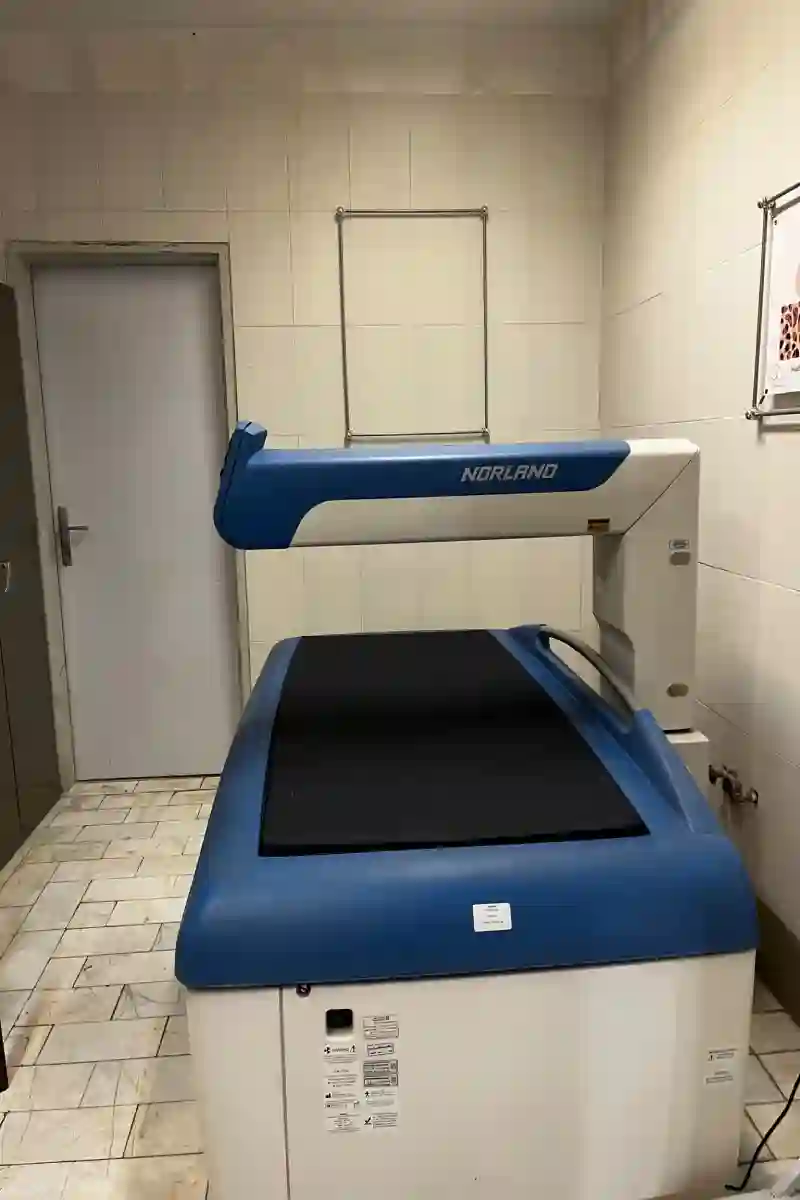

رادیولوژی سونوگرافی فرزانه

#حاملگی #جنسیت #سونوگرافی #تشخیص-صددرصد--جنسیت--جنین #مراقبتهای-دوران-بارداری #سه-یعدی #سونوگرافی-ان-بی #سونوگرافی-ان-تی #غربالگری-سه-ماهه-دوم #فک #عکس-رنگی--معده---اثنی-عشر---روده----کولون #NB #سونوگرافی-nb #جنسیت-جنین #عکس-رنگی-.-معده--.-اثنی-عشر-.--روده--.--کولون #غربالگری-سه-ماهه-اول #NT #ناهنجاری #پانورکس #تشخیص-دقیق-جنسیت--جنین #آنومالی #رادیوگرافی-دندان #دندان #تشخیص-ناهنجاری-جنین #غربالگری- #سونوگرافی-فرزانه #OPG #ستون-فقرات #سونوگرافی-NT #تشخیص-جنسیت--جنین #سونوگرافی-فرزانه